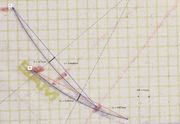

| 22:58, 15 July 2024 | Sirignathograph rotazione asse Y.jpg (file) |  |

246 KB | Gianni | 2 | |